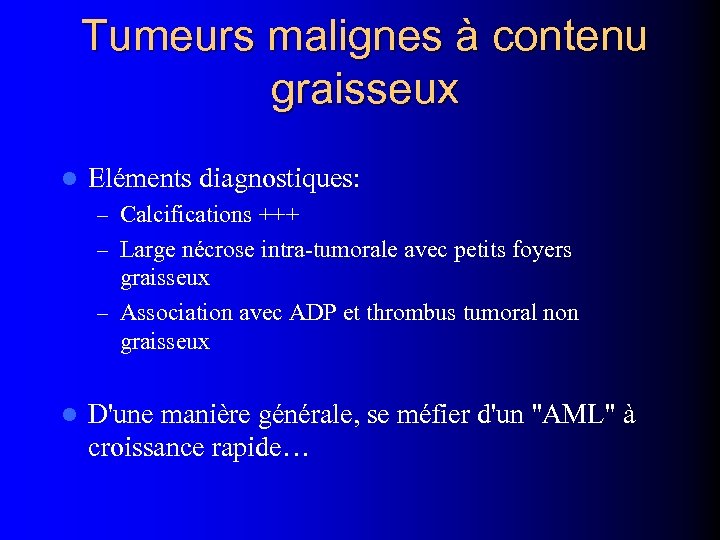

Tumeurs malignes à contenu graisseux l Eléments diagnostiques: – Calcifications +++ – Large nécrose intra-tumorale avec petits foyers graisseux – Association avec ADP et thrombus tumoral non graisseux l D'une manière générale, se méfier d'un "AML" à croissance rapide…

Tumeurs malignes à contenu graisseux l Eléments diagnostiques: – Calcifications +++ – Large nécrose intra-tumorale avec petits foyers graisseux – Association avec ADP et thrombus tumoral non graisseux l D'une manière générale, se méfier d'un "AML" à croissance rapide…